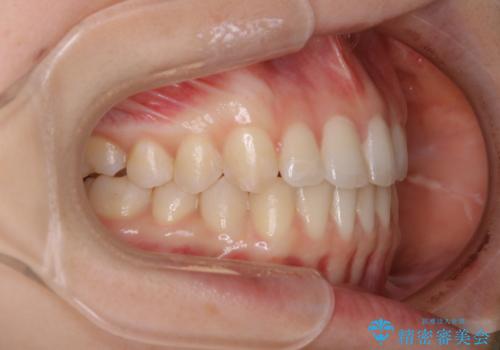

- 上下前歯のがたつきが気になるとご相談にいらした方です。

一見前歯のがたつきだけ改善させれば良い様に見えますが、このがたつきの原因は奥歯の嚙み合わせのズレからくるものであったため、インビザラインFULLで噛み合わせの改善から行っていきました。前歯の角度も改善されたために頑張って唇を閉じる必要がなくなり、横顔のシルエットも綺麗になりました。

前歯のがたつきだけを治そうとした場合、噛み合わせは二の次なってしまう事が多く、せっかく綺麗になった歯並びも後戻りしやすくなります。奥歯の噛み合わせからしっかり機能させることで、長期間にわたって綺麗な歯並びを保ちやすくなります。

インビザライン20時間以上正しく装着していただいたおかげもあり、短期間で治療することが出来ました。